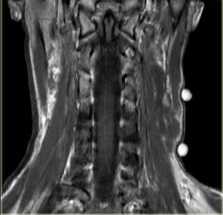

- МРТ. Проводится изолированная МРТ поражённого отдела позвоночника. Исследование позволяет обнаружить невриномы спинномозговых корешков, определить степень спинальной компрессии.

A,B поражение седалищного нерва Т1 и STIR; C поражение языкоглоточного нерва; D Шванома цервикально канала;